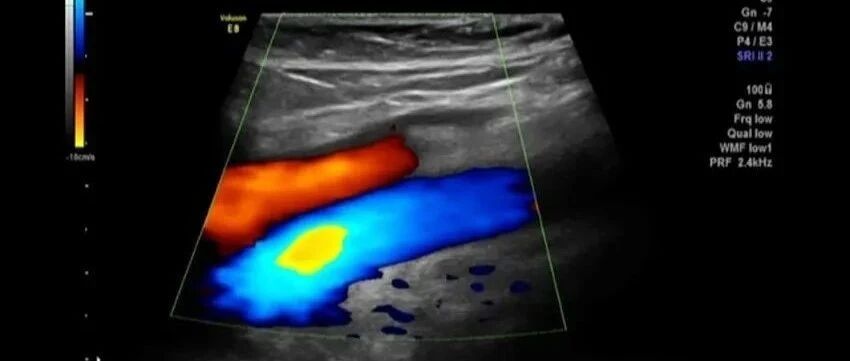

大腿皮下局限性疼性肿块,你怎么考虑? 丁香园超声时间 · 公众号 · 医学 · 1 年前 · |